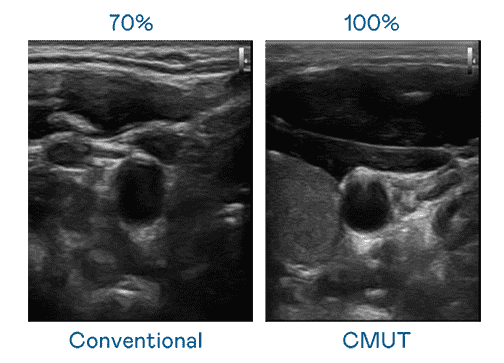

CMUT 技术是一种用电容式微机电元件来产生超音波讯号的技术。。。与传统 PZT 压电式技术相比,,,,CMUT 频宽增加 30%,,更宽频的超音波讯号让影像解析度大幅提升,,,是实现高影像品质医疗超音波扫描、、、促进精准医疗发展的关键技术。。

大频宽带来超清晰影像

超音波影像的解析度高低,,,首先取决于探头能发出的讯号频宽。。。。PG国际 CMUT 可提供高清晰的超音波讯号,,,,提供高频宽、、高灵敏度、、影像纹理细节更高的超音波影像,,协助医护人员缩短影像判读时间及利用精准的医疗影像进行诊断。。